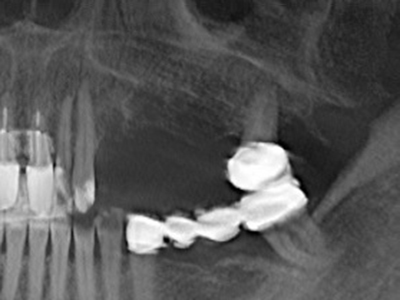

Пиезохирургията има допълнителни предимства при събиране на костни блокове. В допълнение към високата прецизност при остеотомията, описана по-горе, употребата на фините режещи накрайници значително намаляват загубата на материал. Голяма загуба на материал по време на събиране може да се очаква с дебелите накрайници, особено при употреба на борери Линдеман (Lakshmiganthan, Gokulanathan et al. 2012). Базалното разделяне, което е необходимо, особено за присадка на блок при ретромолар, е улеснено от специално създадени правоъгълни триони. В резултат на това, пиезохирургията е разглеждана като прецизна, улеснена и безопасна процедура за събиране на костни блокове в ретромоларното пространство (Happe 2007) (Фиг. 1-12).